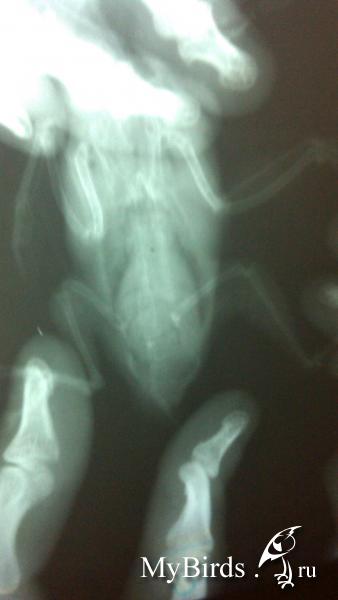

Рентген на ремонте, вот только получилось сделать.

post-64802-1455520113_thumb.jpgpost-64802-1455520130_thumb.jpgpost-64802-1455520146_thumb.jpg

Качество конечно аховое...

Но есть у меня нехорошие подозрения, есть. Поэтому не назначу препараты для выработки мужских ПГ. А наоборот- препараты для хим.кастрации.

Вес птицы-актуальный- напишите, ПЛЗ

41 грамм. Скажите а подозрения это опухоль?

Я узнавал у нас в частной клинике делают какой то цифровой рентген , но он конечно стоит пол моей зарплаты. Но если это критично, я займу денег, сделаю.

Да, я подозреваю новообразование.